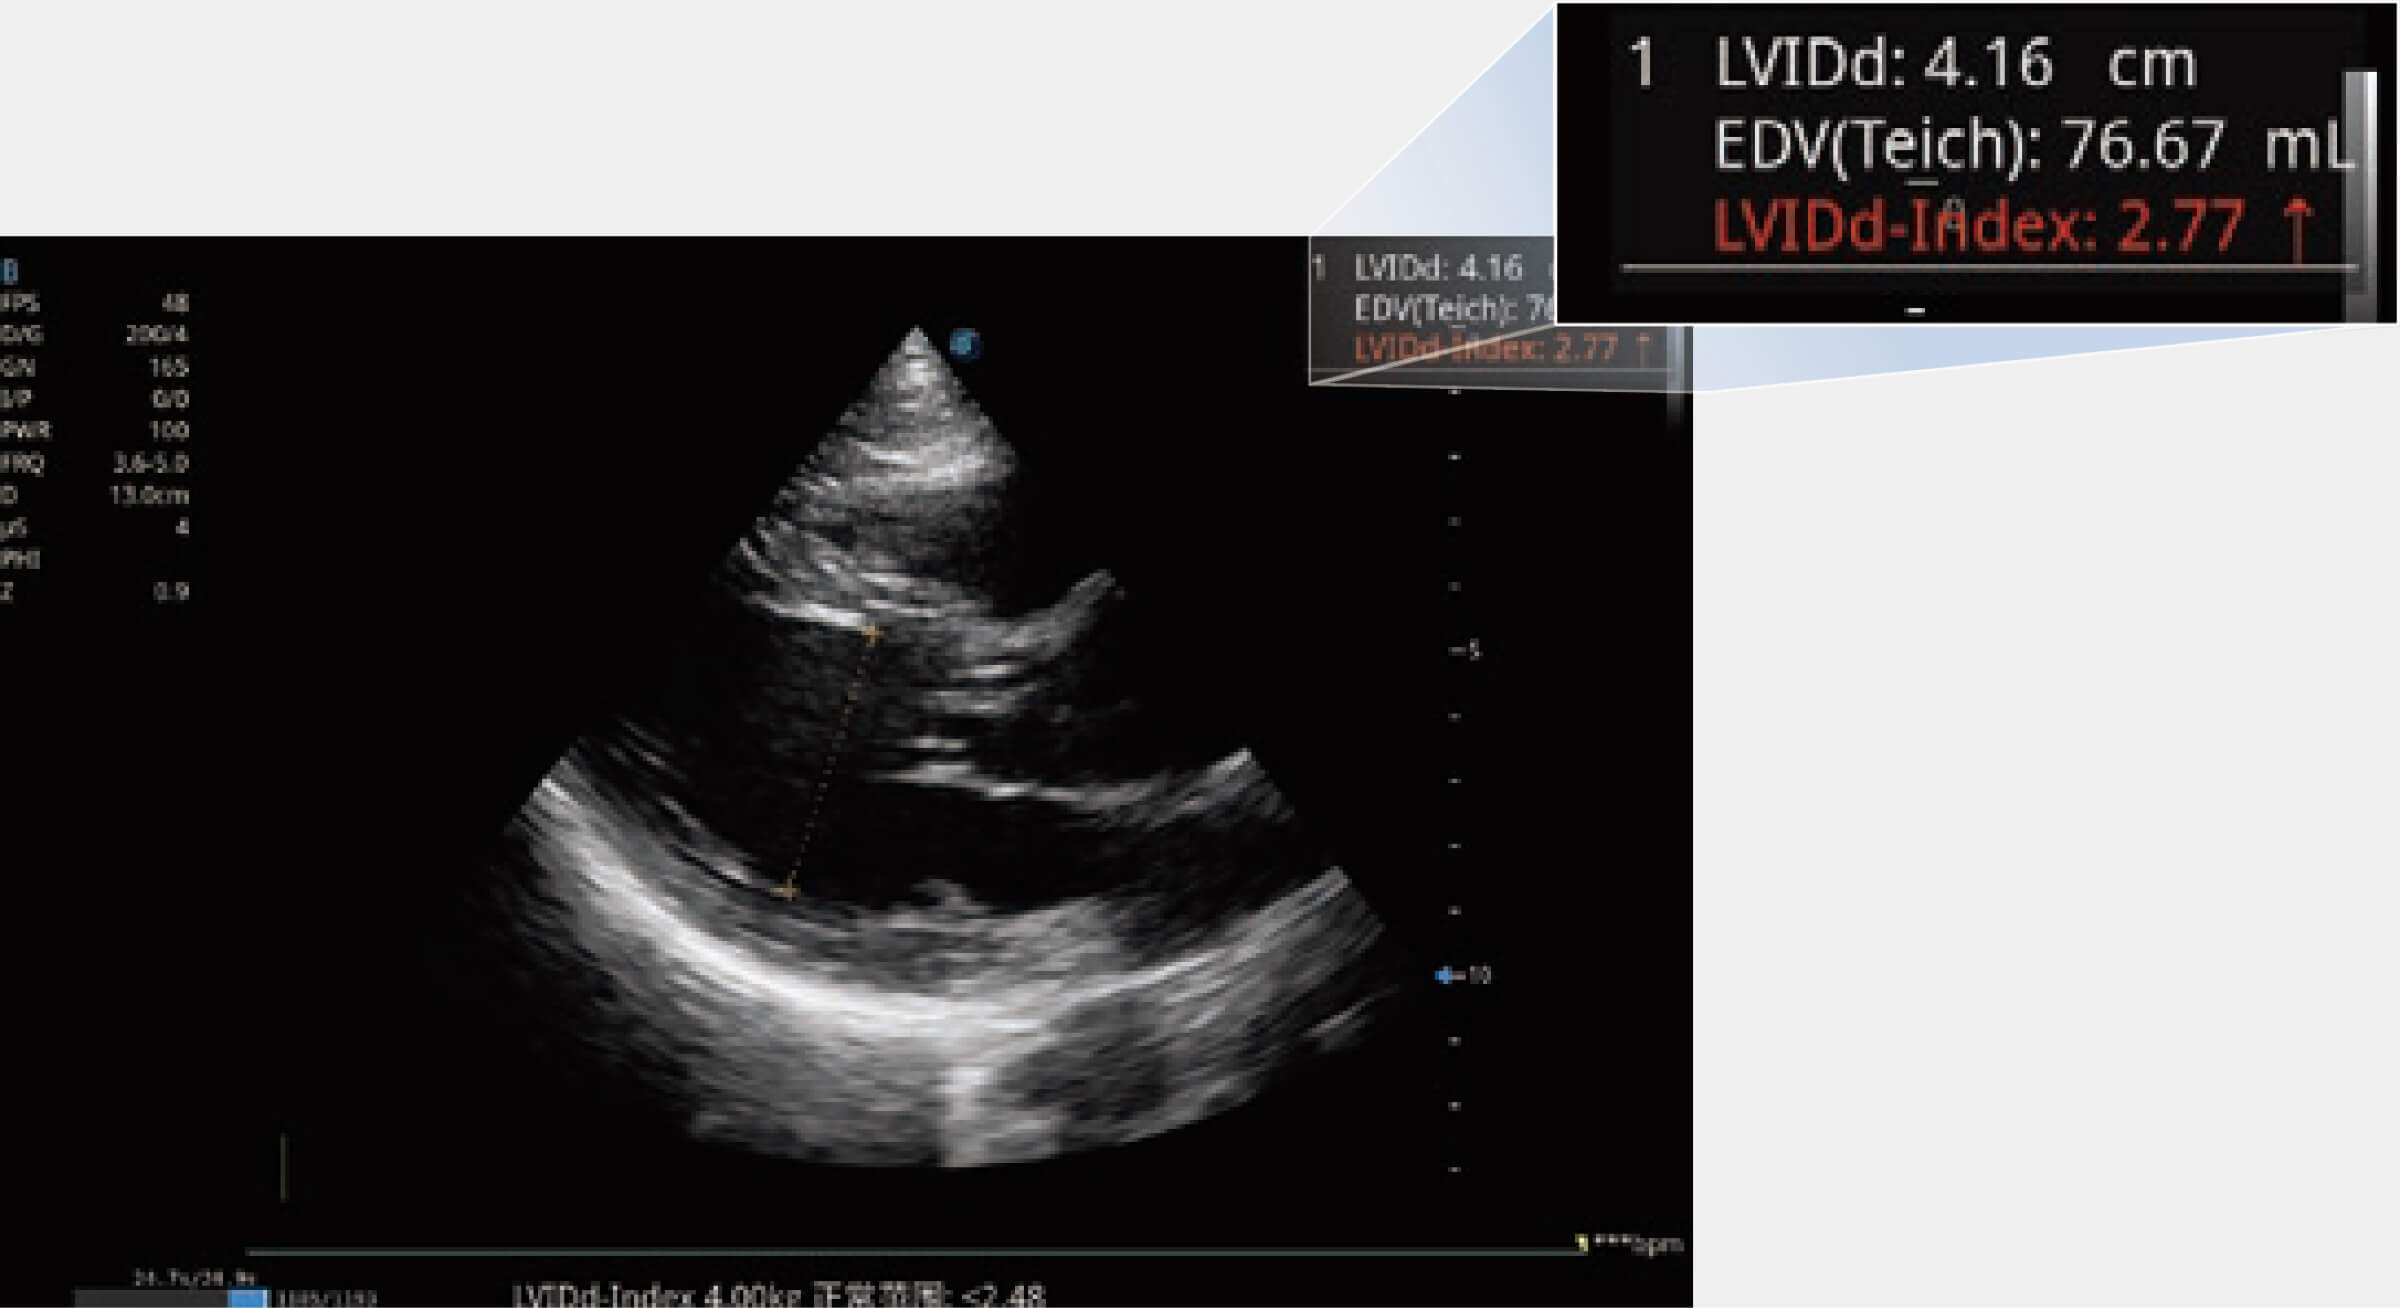

當(dāng)心臟測量結(jié)果超出正常范圍時,可實時預(yù)警提示動物醫(yī)生,減少疾病漏診概率。